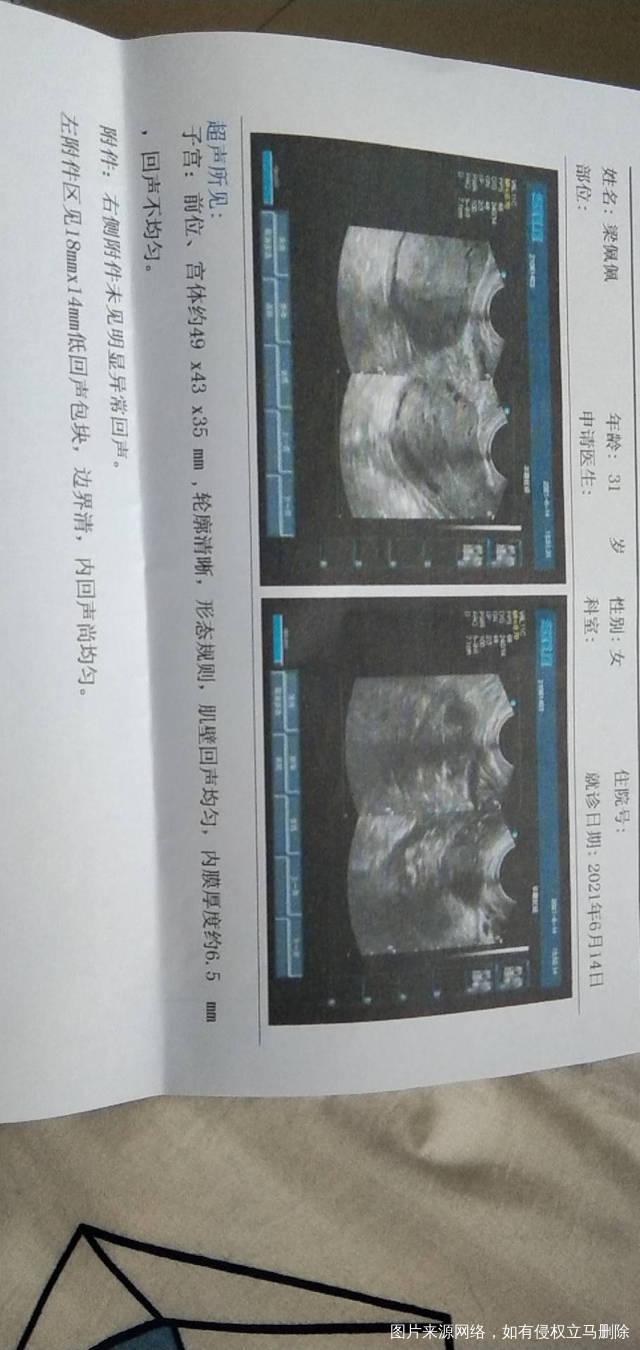

试管移植怀孕57天没有胎心搏动宣告胎停建议药